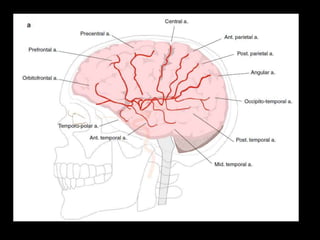

b) Superficial (Cortical) branches :

-Supply a considerable proportion of the superficial

hemispheric cortex

*Arteries to the Frontal lobe :

-These run superiorly after leaving the fissure , from

anterior to posterior :

1-Orbitofrontal artery of the MCA

2-Prefrontal artery (supplies Broca’s area)

3-Precentral artery (or Pre-Rolandic artery of Sillon)

4-Central artery (or artery of the Rolandic fissure)

*Arteries to the Parietal & Occipital lobes:

-These run posterior to the sylvian fissure , from

superior to inferior :

1-Anterior parietal

2-Posterior parietal

3-Angular

4-Occipito-temporal

1-Orbitofrontal , 2-Prefrontal , 3-Precentral , 4-Central , 5-Anterior parietal , 6-Post

parietal , 7-Angular , 8-Occipito-temporal , 9-Posterior temporal , 10-Middle

temporal , 11-Anterior temporal , 12-Tempero-polar

*Arteries to the Temporal lobe :

-These run inferiorly after leaving the lateral

sulcus of the sylvian fissure and are arranged

from anterior to posterior :

1-Temporo-polar

2-Anterior temporal

3-Middle temporal

4-Posterior temporal